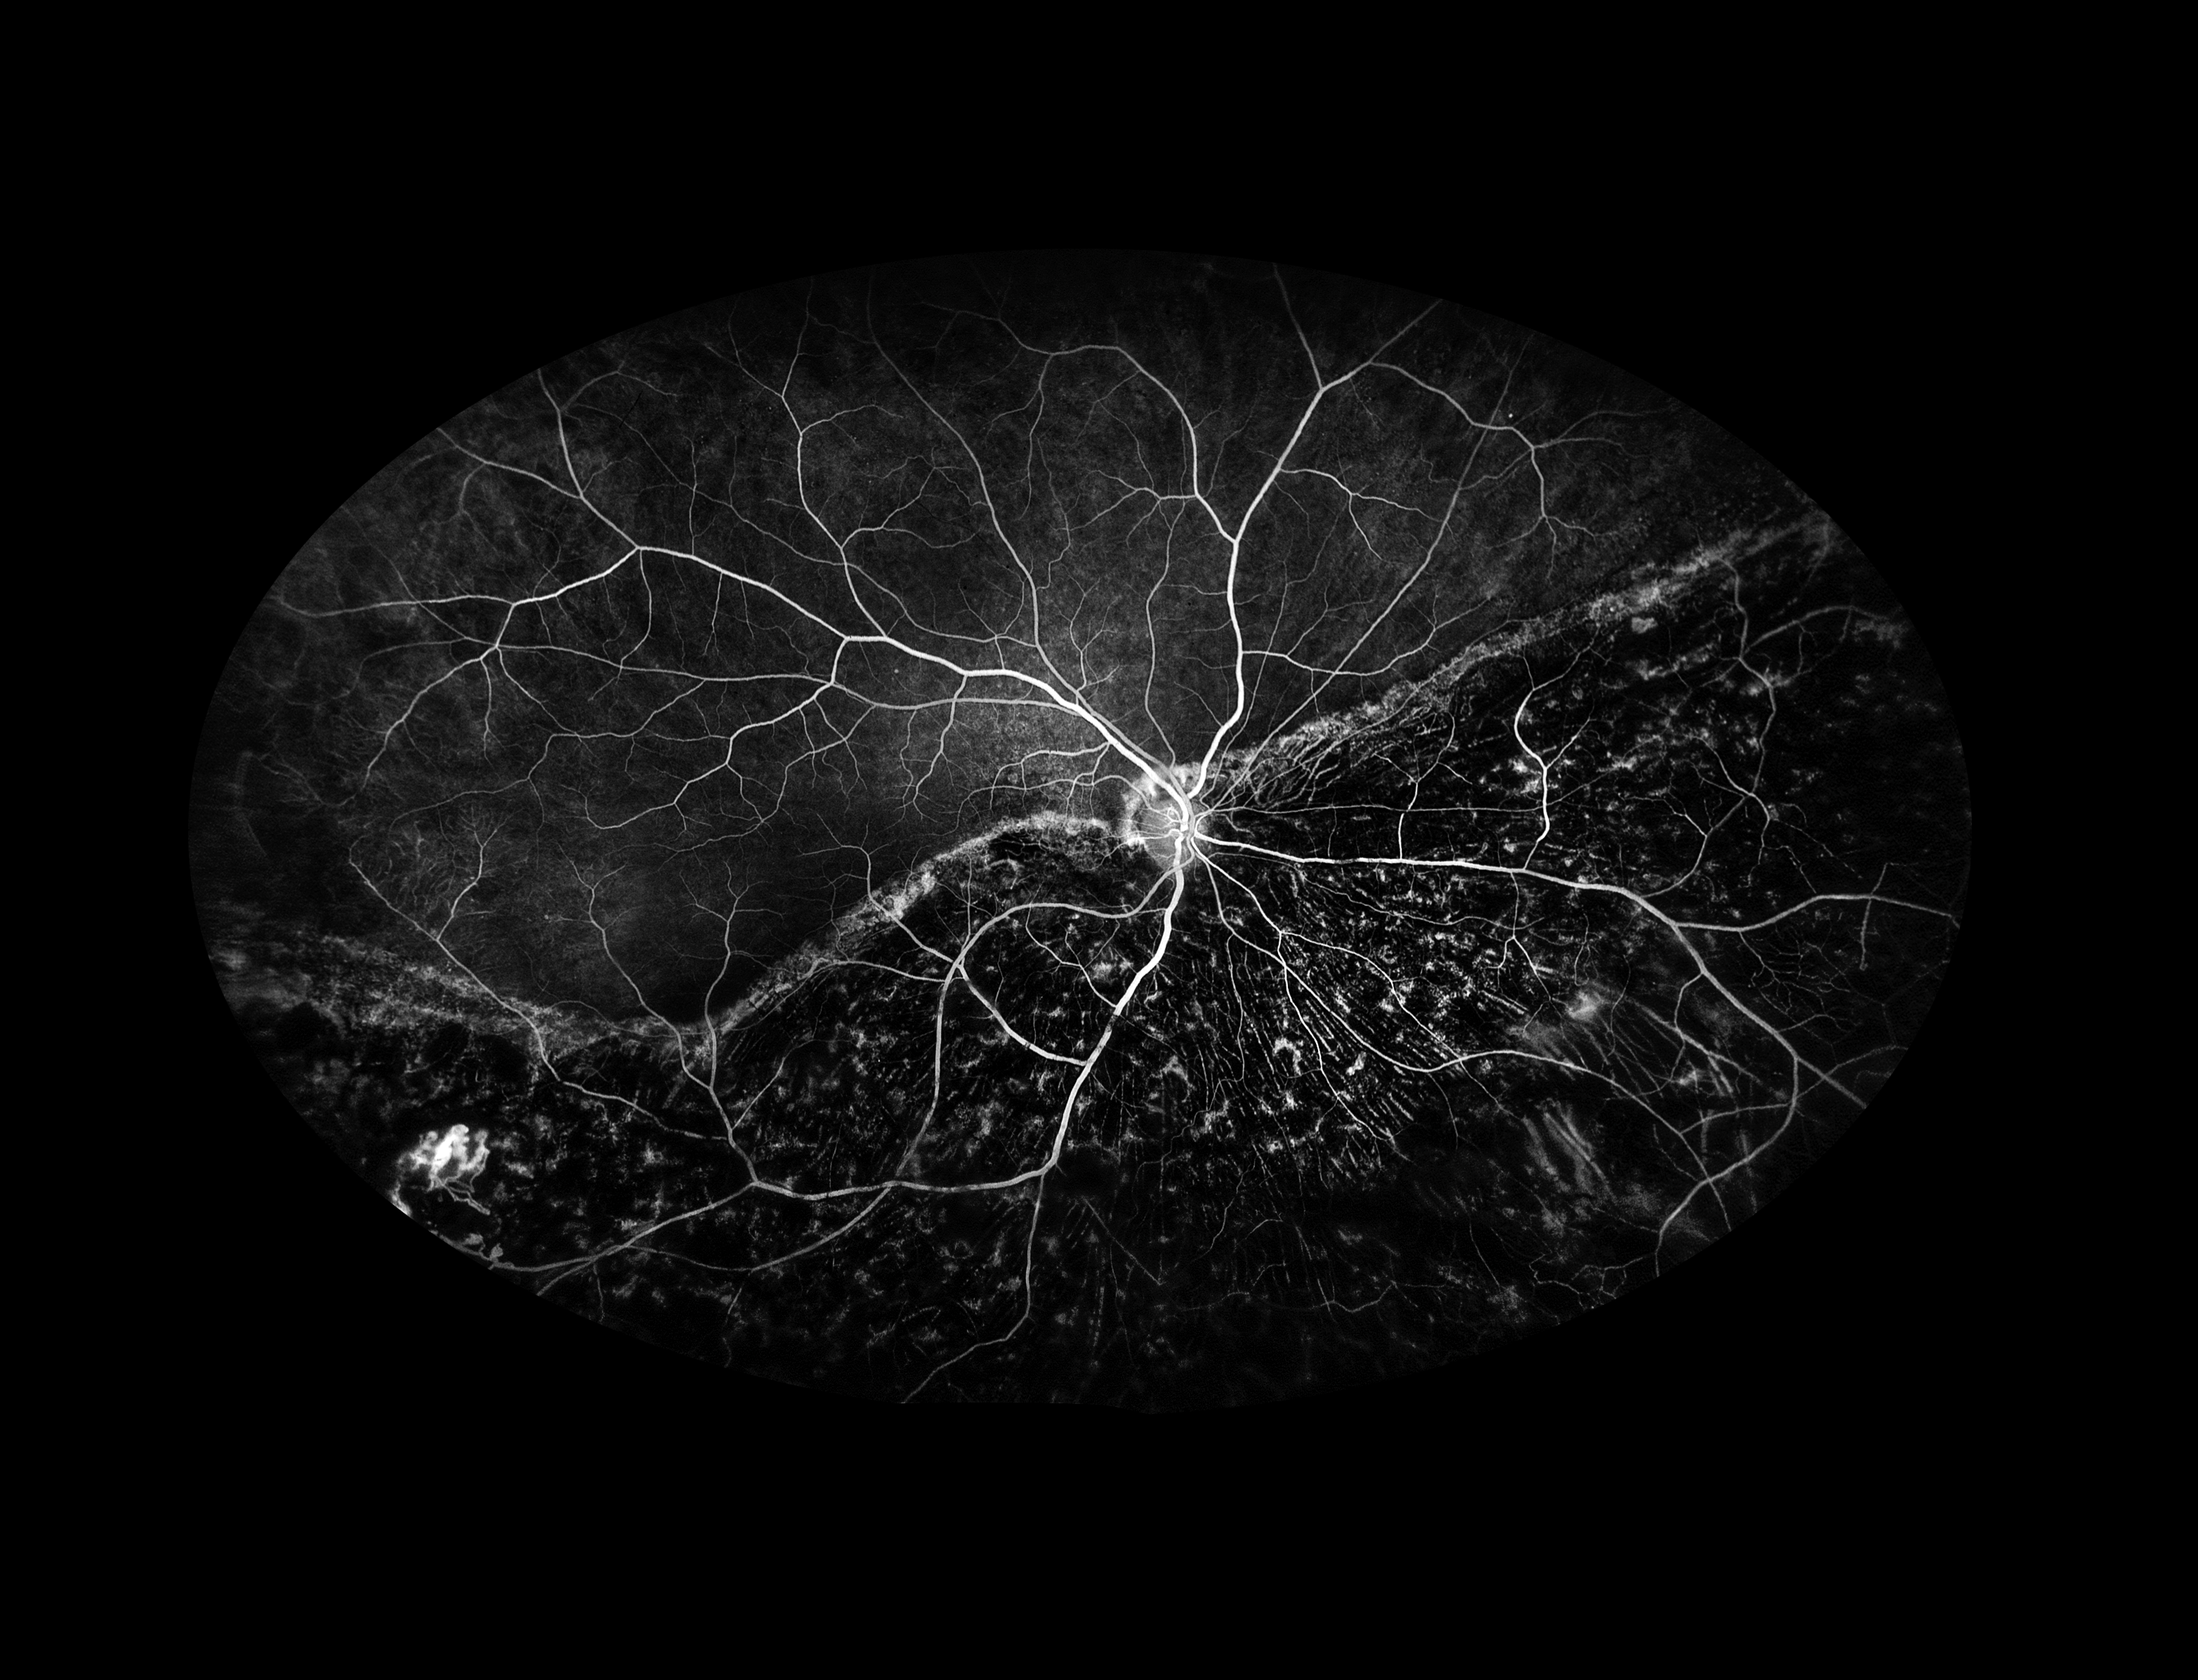

Ocular Histoplasmosis Presented by Judith Gulian, OCT-C This photograph received Honorable Mention, Fluorescein Angiography (UWF) in the 2025 OPS Scientific Exhibit. Filed Under Cornea OPS Photo